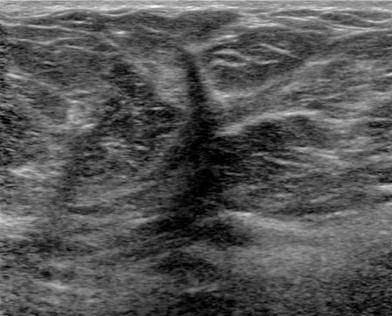

The target dataset was developed from 35 breast ultrasound scans that were segmented by an image-processing expert with extensive experience in breast lesion segmentation (the second author). The images, collected from the Web, are of different dimensions, ranging from to pixels (Figure 3, images resized for sake of illustration). These are the same images used to introduce EFIS originally [1].

Ultrasound images are generally difficult to segment, primarily due to the presence of speckle noise and low level of local contrast. It should be noted that the segmentation of ultrasound actually does require a complete processing chain, (including proper preprocessing and post-processing steps). However, the purpose of using these images was solely to demonstrate that the accuracy of the segmentation can be increased with the application of SC-EFIS.